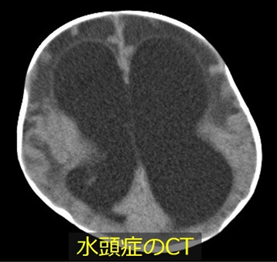

水頭症とは、何らかの原因で髄液の循環や吸収が障害され頭の中に髄液が貯留している疾患です。水頭症の原因には、中脳水道狭窄症や脊髄髄膜瘤に伴う先天性のもの、早産低出生体重児での脳室内出血や脳腫瘍に伴う後天性のものなど多数あります。

手術は大きく分けて二種類です。一つ目は脳室腹腔シャント術(V-Pシャント術)で、脳室と腹腔をシャントチューブでつないで余分な髄液をおなかに流すものです。もう一つは第Ⅲ脳室底開窓術という方法で、内視鏡を使用して脳室の底に穴を開け髄液の流通路を作成します。どの治療法がお子さんにとってベストなのかは水頭症の状態によって異なります。脳の発達に悪影響をもたらさないよう必要な時期にきちんと治療を受けることが一番大切です。